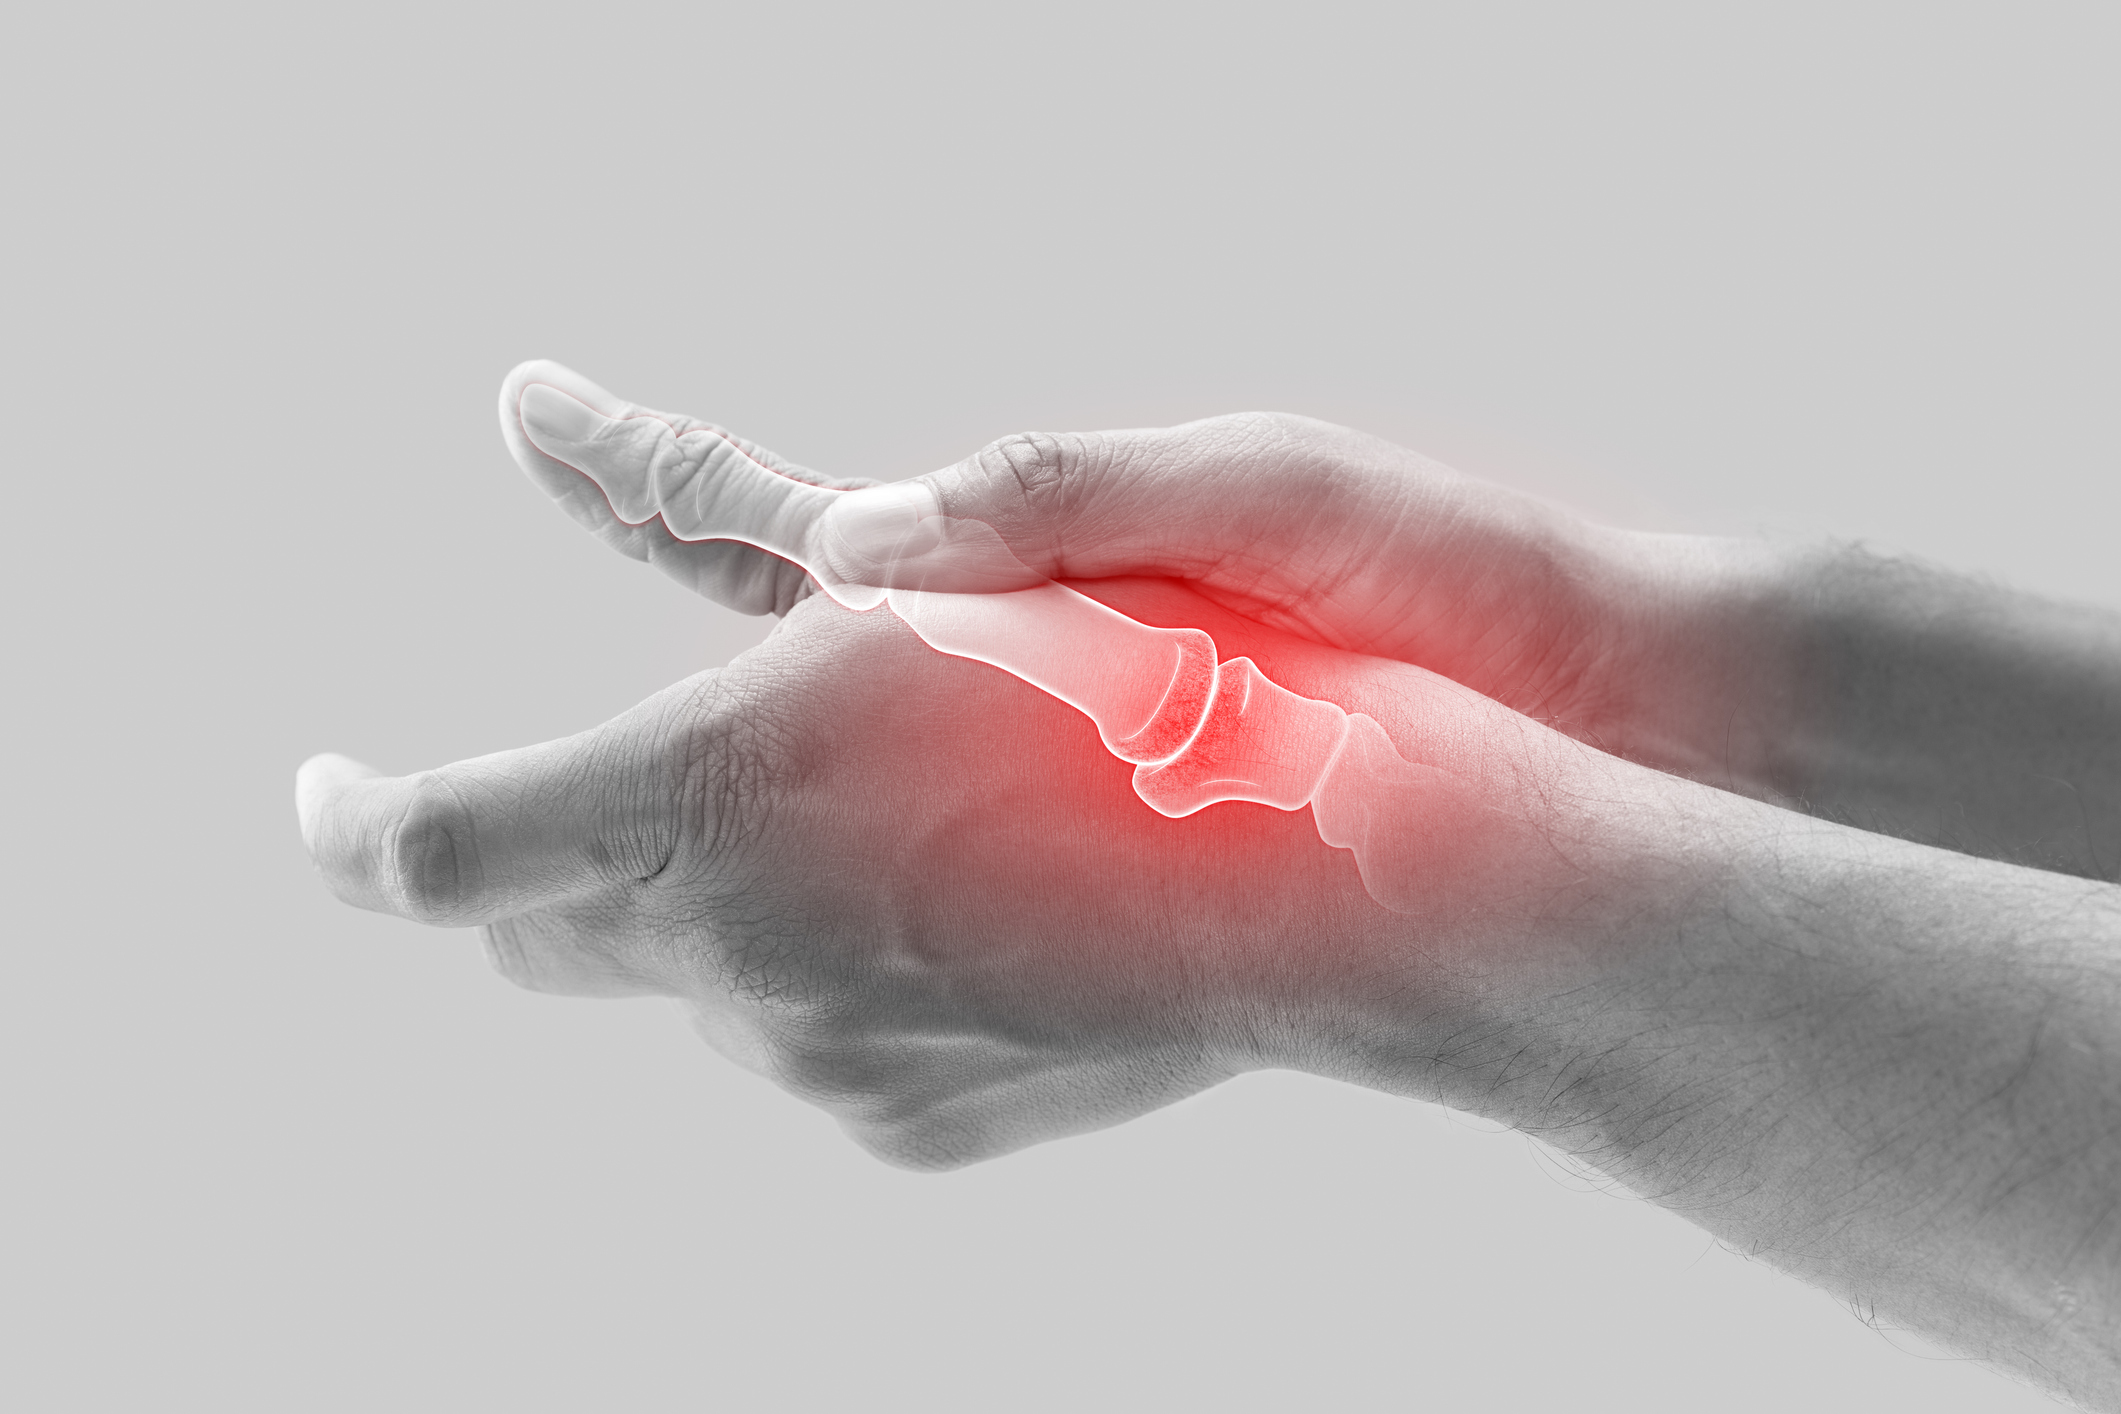

Low-Dose Radiation Therapy in Osteoarthritis: A Review

Despite its international clinical use, low dose radiation therapy (LDRT) in the treatment of osteoarthritis (OA) is minimally used in the United…

LDRT for osteoarthritis: Challenges for future studies

Osteoarthritis (OA) is increasingly one of the most common and socioeconomically relevant diseases in the Western world. Low-dose radiotherapy…